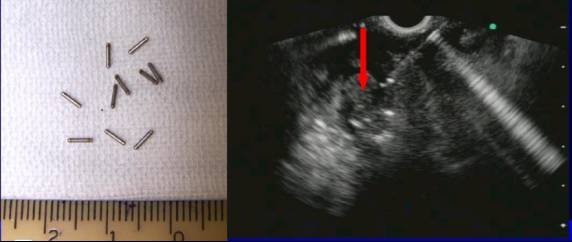

4)超声内镜引导下植入放射性125I粒子治疗中晚期胰腺癌。

适应症:

1、未经治疗的原发肿瘤,如胰腺癌、肝左叶癌、腹膜后肿瘤等;

2、患者不愿意进行根治或无法手术的腹腔肿瘤;

3、转移性肿瘤病灶或术后孤立性肿瘤转移灶;

4、外照射效果不佳或失败的腹腔肿瘤。